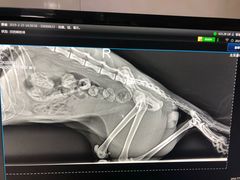

• 康乐宝动物医院

• -康乐宝动物医院

路小新 | 19-02-23